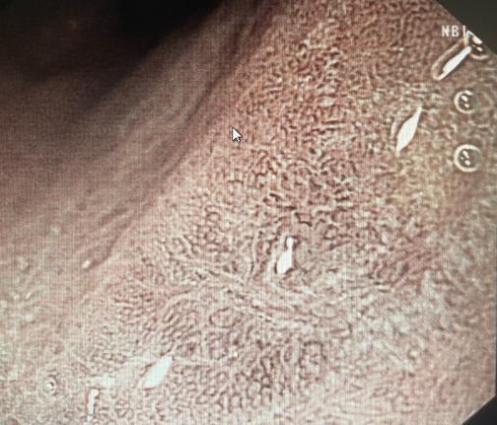

12月9日,张绍仁和周春华在消化内镜中心对患者进行放大内镜检查。经过评估,他们认为自己有内镜下治疗的指征,并决定进行消化内镜ESD手术治疗。手术持续了5个小时,张绍仁彻底剥离了病人的疾病,保留了整个胃,避免了手术的巨大创伤。术后患者恢复良好,一周后顺利出院。